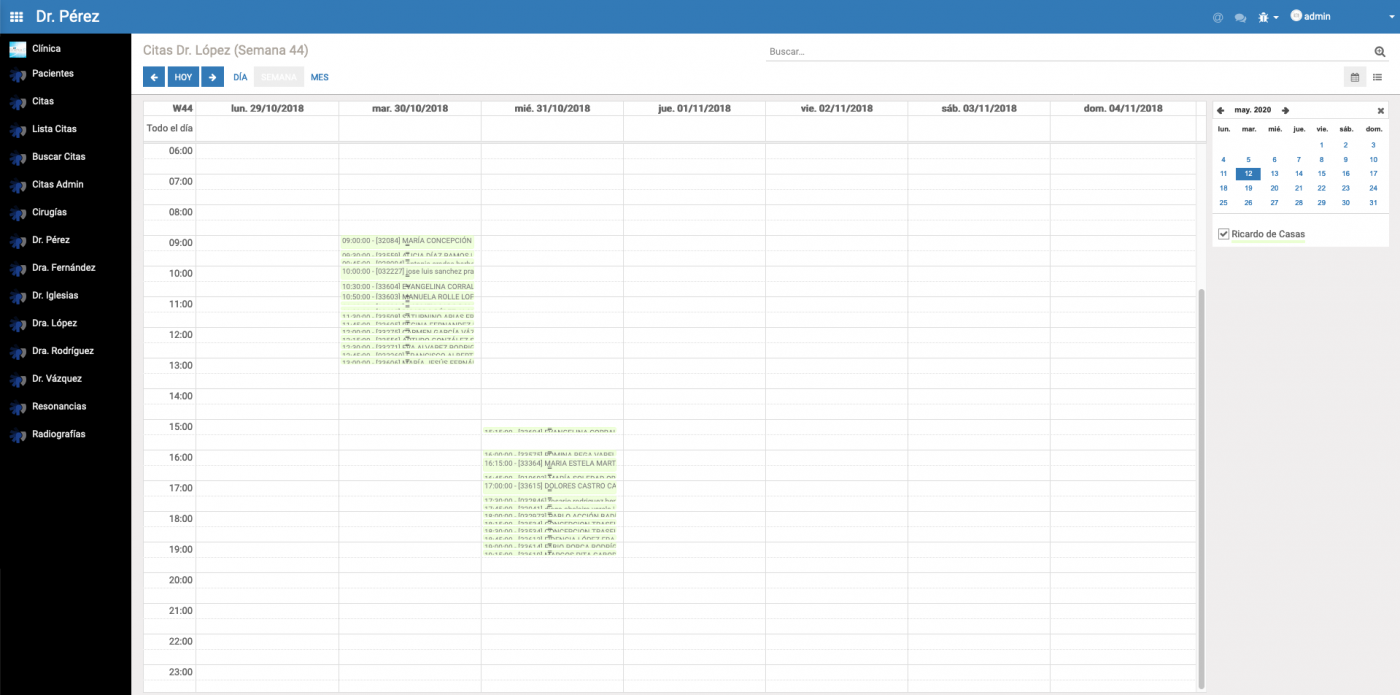

Módulo

Médicos

Medical Sinerkia proporciona la gestión de médicos para configurar su disponibilidad semanal de tal forma que permita un mayor control en la asignación de las citas.

Módulo

Citas

En Medical Sinerkia pensamos que el módulo de citas es el núcleo del la gestión de la clínica. Para ello toda la información de la consulta se mantiene integrada en la cita: Acto médico, cirugías, documentos asociados, etc.

Además la herramienta proporciona diferentes vistas, calendario, listados, detalle de la cita, para facilitar el acceso a las consultas y filtros que permiten agrupar las consultas.